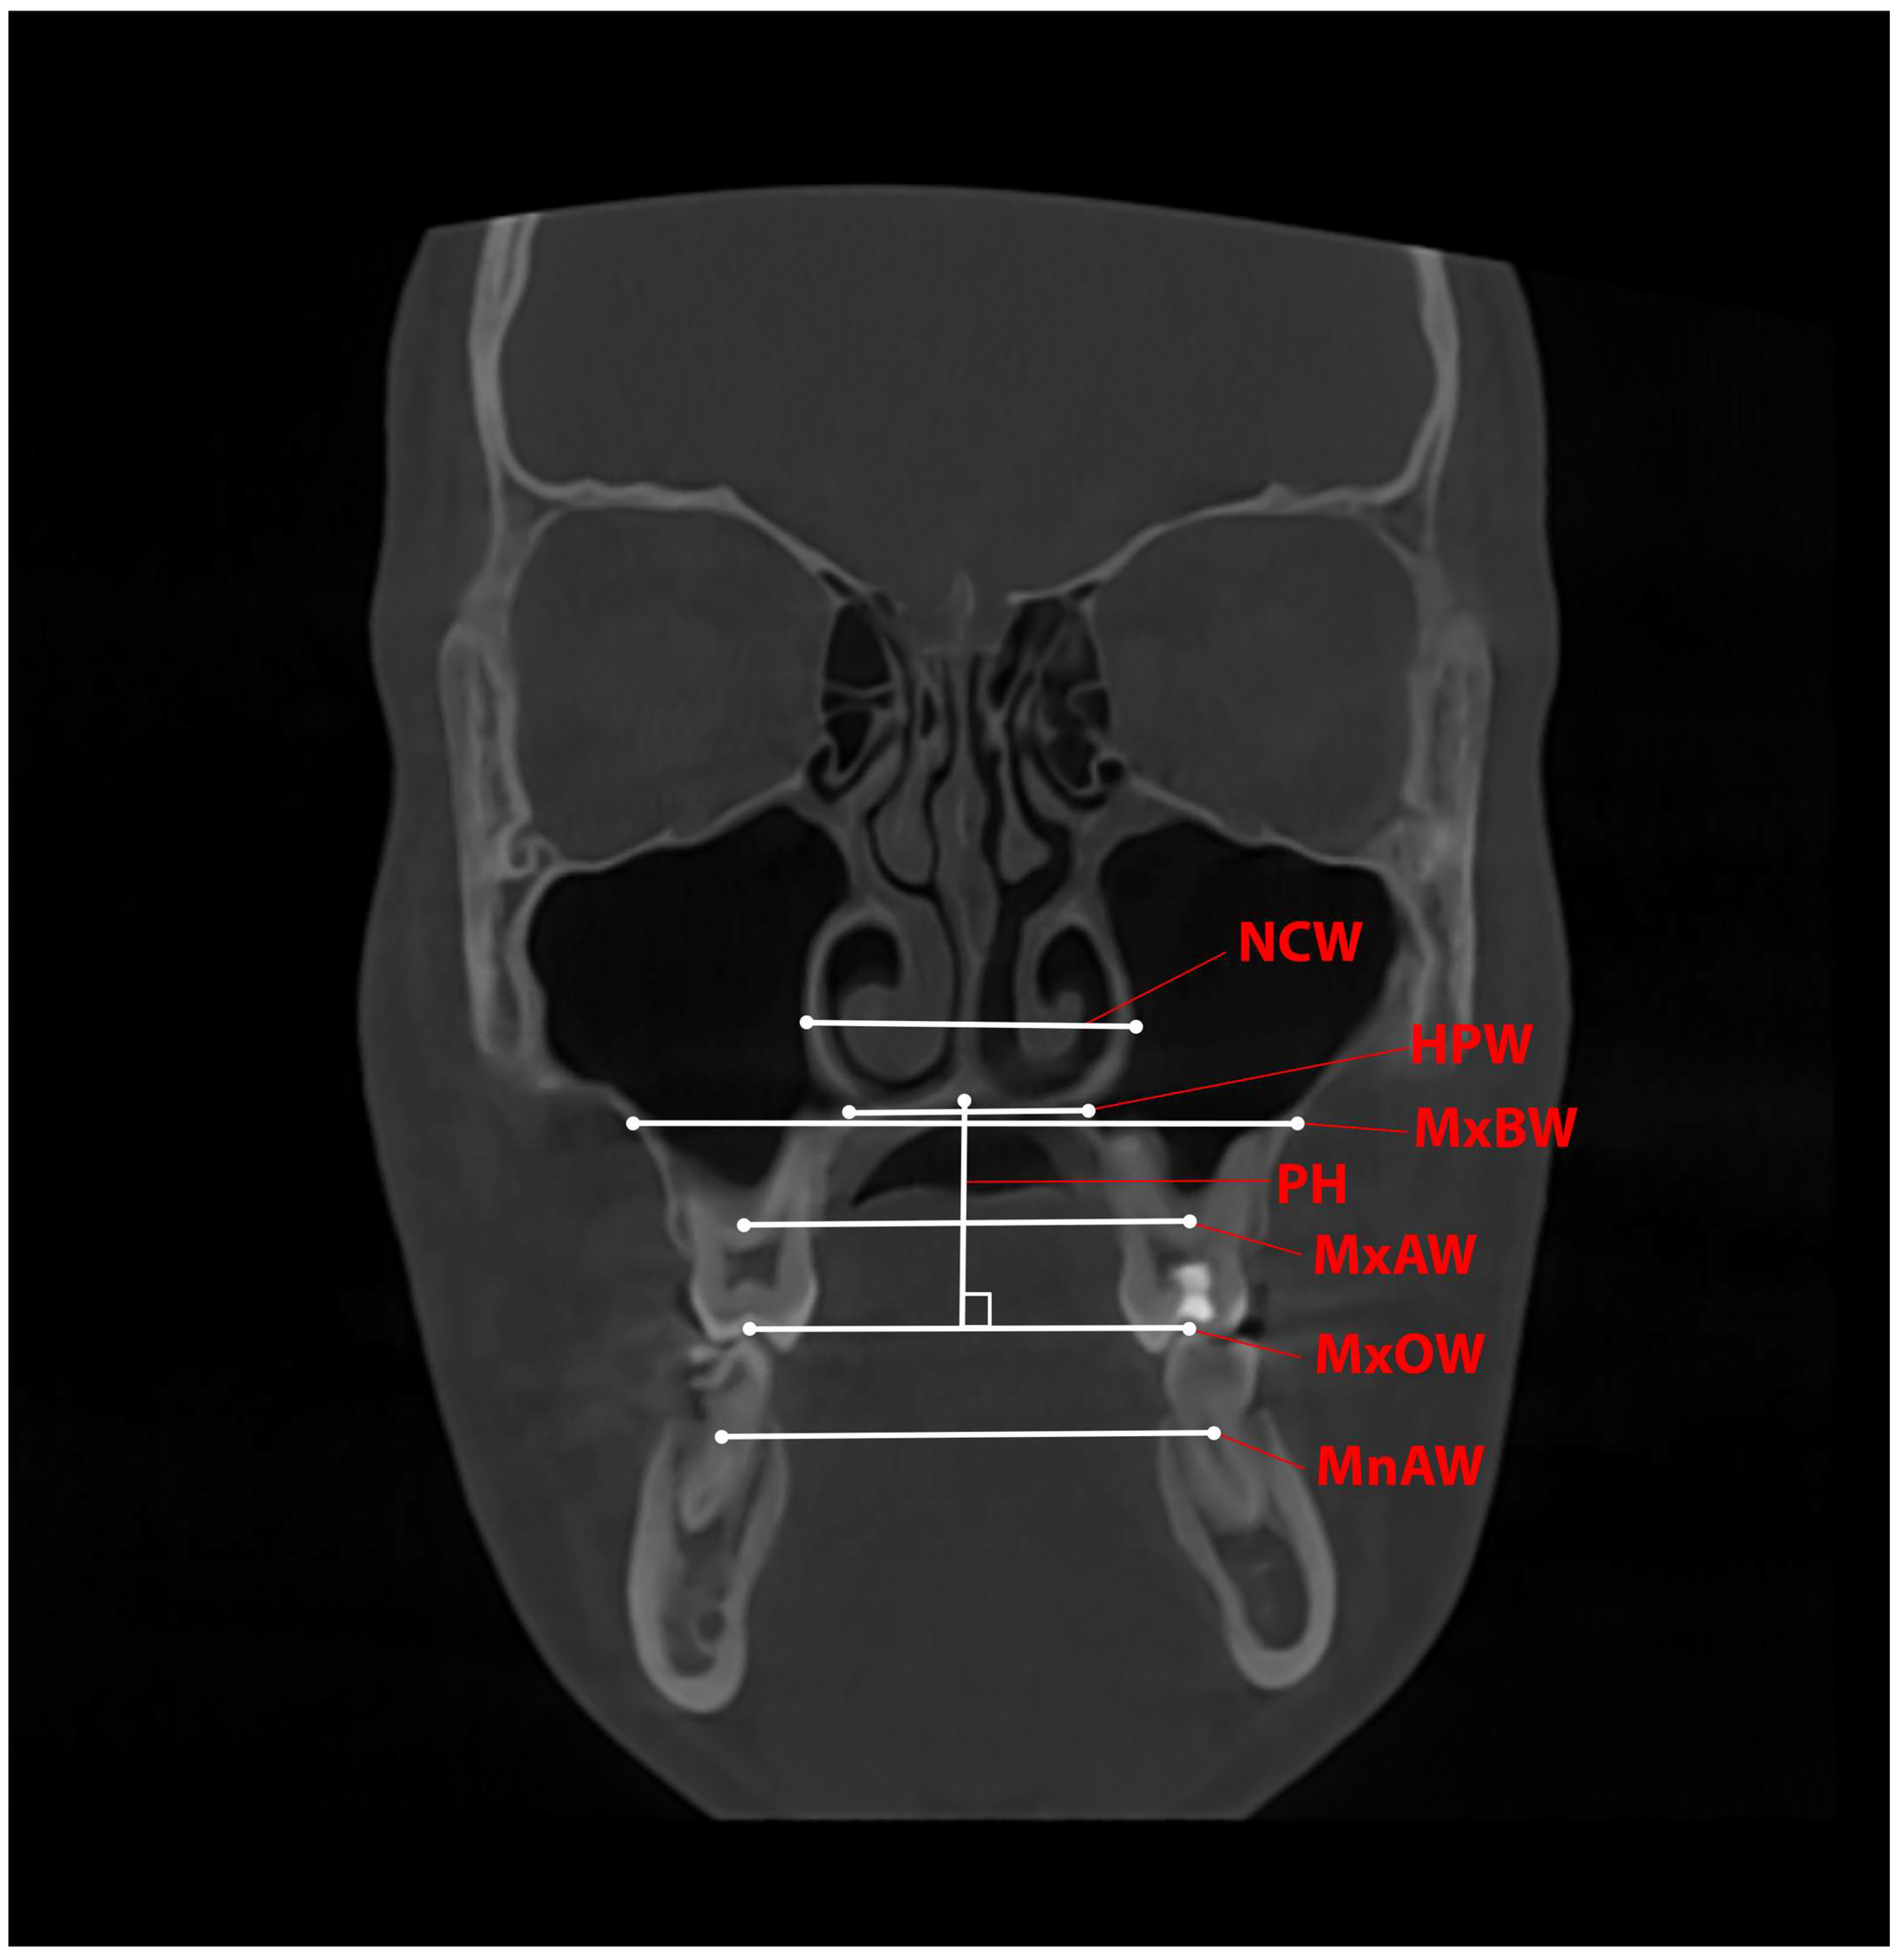

| Variable | Definition |

|---|---|

| MxOW—Maxillary Occlusal Width | The distance between the central fossa of the upper first molars |

| MxAW—Maxillary Alveolar Width | The distance between the centres of resistance (CRs) of the upper first molars |

| MxBW—Maxillary Basal Width | The distance between the intersection of the horizontal line passing through the top of the palate with the maxillary lateral wall |

| MnAW—Mandibular Alveolar Width | The distance between the centres of resistance (CRs) of the lower first molars |

| NCW—Nasal Cavity Width | The distance between the widest parts of the lateral nasal walls |

| HPW—Hard Palatal Width | The distance between the most lateral points of the bony palate |

| PH—Palatal Height | The perpendicular distance from MxOW to the suture of the hard palate |

| TDI—Transverse Discrepancy Index | The difference between MxAW1 and MnAW1 TDI < −2.5 mm with no discrepancy when TDI > −2 mm. |